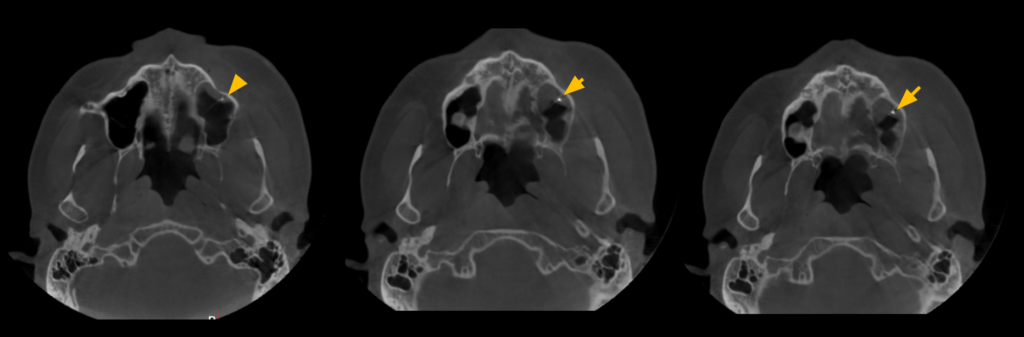

Paciente masculino de 45 años acude para una evaluación general. A la evaluación de la radiografía panorámica (Figura 1) se observa engrosamiento de la mucosa de seno maxilar izquierdo además de una imagen radiopaca proyectada en seno maxilar izquierdo; así mismo en pieza 26 se observa restauración coronaria, sellado cameral y obturación de conductos. A la evaluación de la tomografía volumétrica (cone beam) bimaxilar en los cortes axiales (Figura 2), coronales (Figura 3) y transaxiales (Figura 4) se observa que la pieza 26 presenta obturación de conductos además del engrosamiento de seno maxilar izquierdo e imagen hiperdensa de alta densidad, de

forma irregular, localizada en la mucosa de seno maxilar izquierdo.

CORTES AXIALES